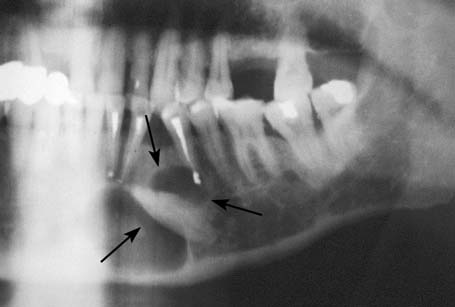

Удаление ретенированных дистопированных премоляра и моляра нижней челюсти

1. Исходная клиническая картина. Рентгенологическое обследование

Фото 1.1. Ретенированные дистопированные 2-ой премоляр и 1-ый моляр нижней челюсти.

Фото 1.2. Плотный фиссурно-бугорковый контакт коронок зубов. Конвергенция корней 1-го моляра.

Фото 1.3. Мезио-дистальная локализация ретенированных зубов.

Горизонтальное положение в челюсти.

Фото 1.4. Дистопированные зубы укрыты снаружи костным краем замыкающей пластинки.

Фото 1.5. Проекция выхода канала нижнечелюстного нерва в области ретенированных зубов.